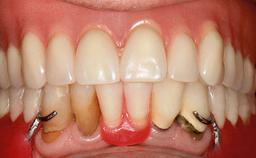

The patient presented with root fracture of the right central incisor with associated distal bone loss. After sectioning and extraction of the fractured root the distal papilla was lost, creating an esthetic compromise. This case demonstrates an option for treating this esthetic compromise. Early (Type 2) implant placement was performed at 7 weeks with simultaneous horizontal and vertical augmentation using Bio-Oss and Bio-Gide (Geistlich). After 3 months a connective tissue graft was performed at the time of implant exposure. Despite these surgical procedures, the papilla could not be recovered. As a result, a prosthetic solution was necessary.

| Soft Tissue Contour and Volume | Significantly deficient |